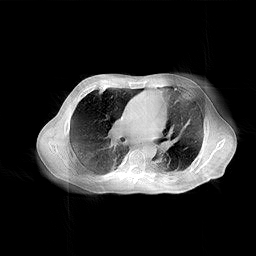

4.5.2 Quantum Noise

where is the blank measurement (). It is worth mentioning that the sinogram measurements employed in this study are derived from simulations, as opposed to being sourced from an actual instrument. Thus, here is a parameter for relative measurement. Throughout the experiments, is assigned values ranging from to , which correspond to sinogram SNR (dB) values of . It is worth mentioning that analogous experiments were conducted under both few-view and limited-angle scenarios, with the proposed method demonstrating a marked superiority over other methods across all conditions. This enhancement, however, is primarily attributed to the exceptional performance of the proposed method under sparse-measurement circumstances, rather than an increased resistance to noise. To facilitate an equitable comparison, the results displayed in Fig.11 are solely derived from the full-view scenario, which encompasses an angular range of with one view per degree.

(a) ASD-POCS (19.92dB)

(b) RBP-DIP (23.82dB)

(c) DIP (21.88dB)

(d) MED50 (15.61dB)

In practical applications, the imaged object might exhibit inconsistencies with the training dataset due to various non-ideal factors. The rotation operation in Section 4.5 serves as a simplified simulation of such discrepancies, which may arise from differing poses of patients. The impact on reconstruction accuracy is shown in Fig.9. The comparison between Fig.5b and Fig.9 reveals that the pre-trained MED50 method is predominantly affected by a considerable decline in SNR. The reconstruction results are also presented in Fig.10. In contrast to the first row of Fig.7, the MED50 reconstruction result lacks a completely black background and exhibits horizontal artifacts in the non-empty region. This observation suggests that MED50 cannot effectively handle the perturbations in the inference data.

Additionally, experiments were conducted under low-dose conditions, as demonstrated in Fig.11. MED50 was found to be the most vulnerable to sinogram noise, while RED-CNN exhibited relative insensitivity to perturbations due to its patch-based learning approach.

The proposed RBP-DIP framework does not necessitate any training images and attains the highest reconstruction accuracy in both experiments. Moreover, additional constraints or regularizations can be directly incorporated into the objective function or indirectly integrated into the RBP connection, enabling enhanced handling of various factors without retraining.